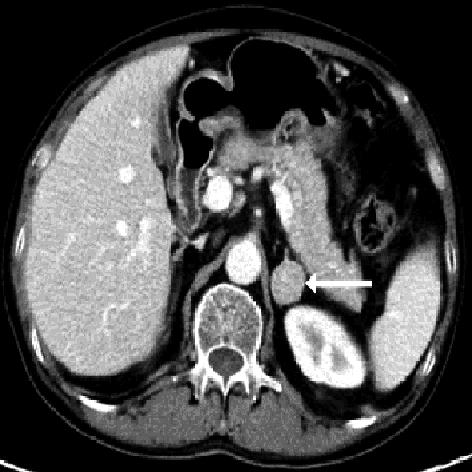

• 嗜铬细胞瘤及副神经节瘤不同生化表型的CT征象对比研究

2024, 49(2):203-209. DOI: 10.13406/j.cnki.cyxb.003433

摘要 (51) HTML (33) PDF 3.10 M (96) 评论 (0) 收藏

摘要:目的 分析生化阴性嗜铬细胞瘤及副神经节瘤(pheochromocytomas and paragangliomas,PPGLs)的电子计算机断层扫描(computed tomography,CT)征象是否有别于生化阳性PPGLs,同时了解生化阳性PPGLs不同表型的CT征象是否存在差异。方法 回顾性分析131例PPGLs患者的术前腹部增强CT图像,包括肿瘤位置、大小、形态、囊变坏死、液-液分层、钙化、向心结节状强化、肿瘤内粗大血管、强化包膜、绝对廓清率及相对廓清率。根据生化水平,将患者分为生化阳性组和阴性组,阳性组进一步分为去甲肾上腺素型、肾上腺素型及多巴胺型。比较各组及各表型间的CT征象差异。结果 相较于生化阴性组,阳性组PPGLs更大(Z=-2.064,P=0.039)、囊变坏死(χ2=6.610,P=0.010)及向心结节状强化(χ2=3.909,P=0.048)的比例更高;相较于去甲肾上腺素型,肾上腺素型PPGLs更大(Z=-2.036,P=0.042)、强化包膜比例更高(χ2=7.242,P=0.007)。结论 肿瘤大小、囊变坏死及向心结节状强化的CT征象有助于术前诊断生化阴性PPGLs,肿瘤大小及强化包膜有助于解释去甲肾上腺素型及肾上腺素型PPGLs不同临床表现产生的机制。